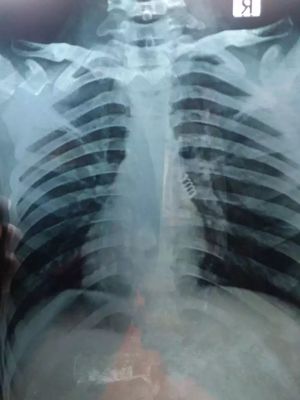

A 14 year male child asymptomatic.routine check up for cough for 3 days xray shows fb

Left inf. bronchus, rigid bronchoscopy.